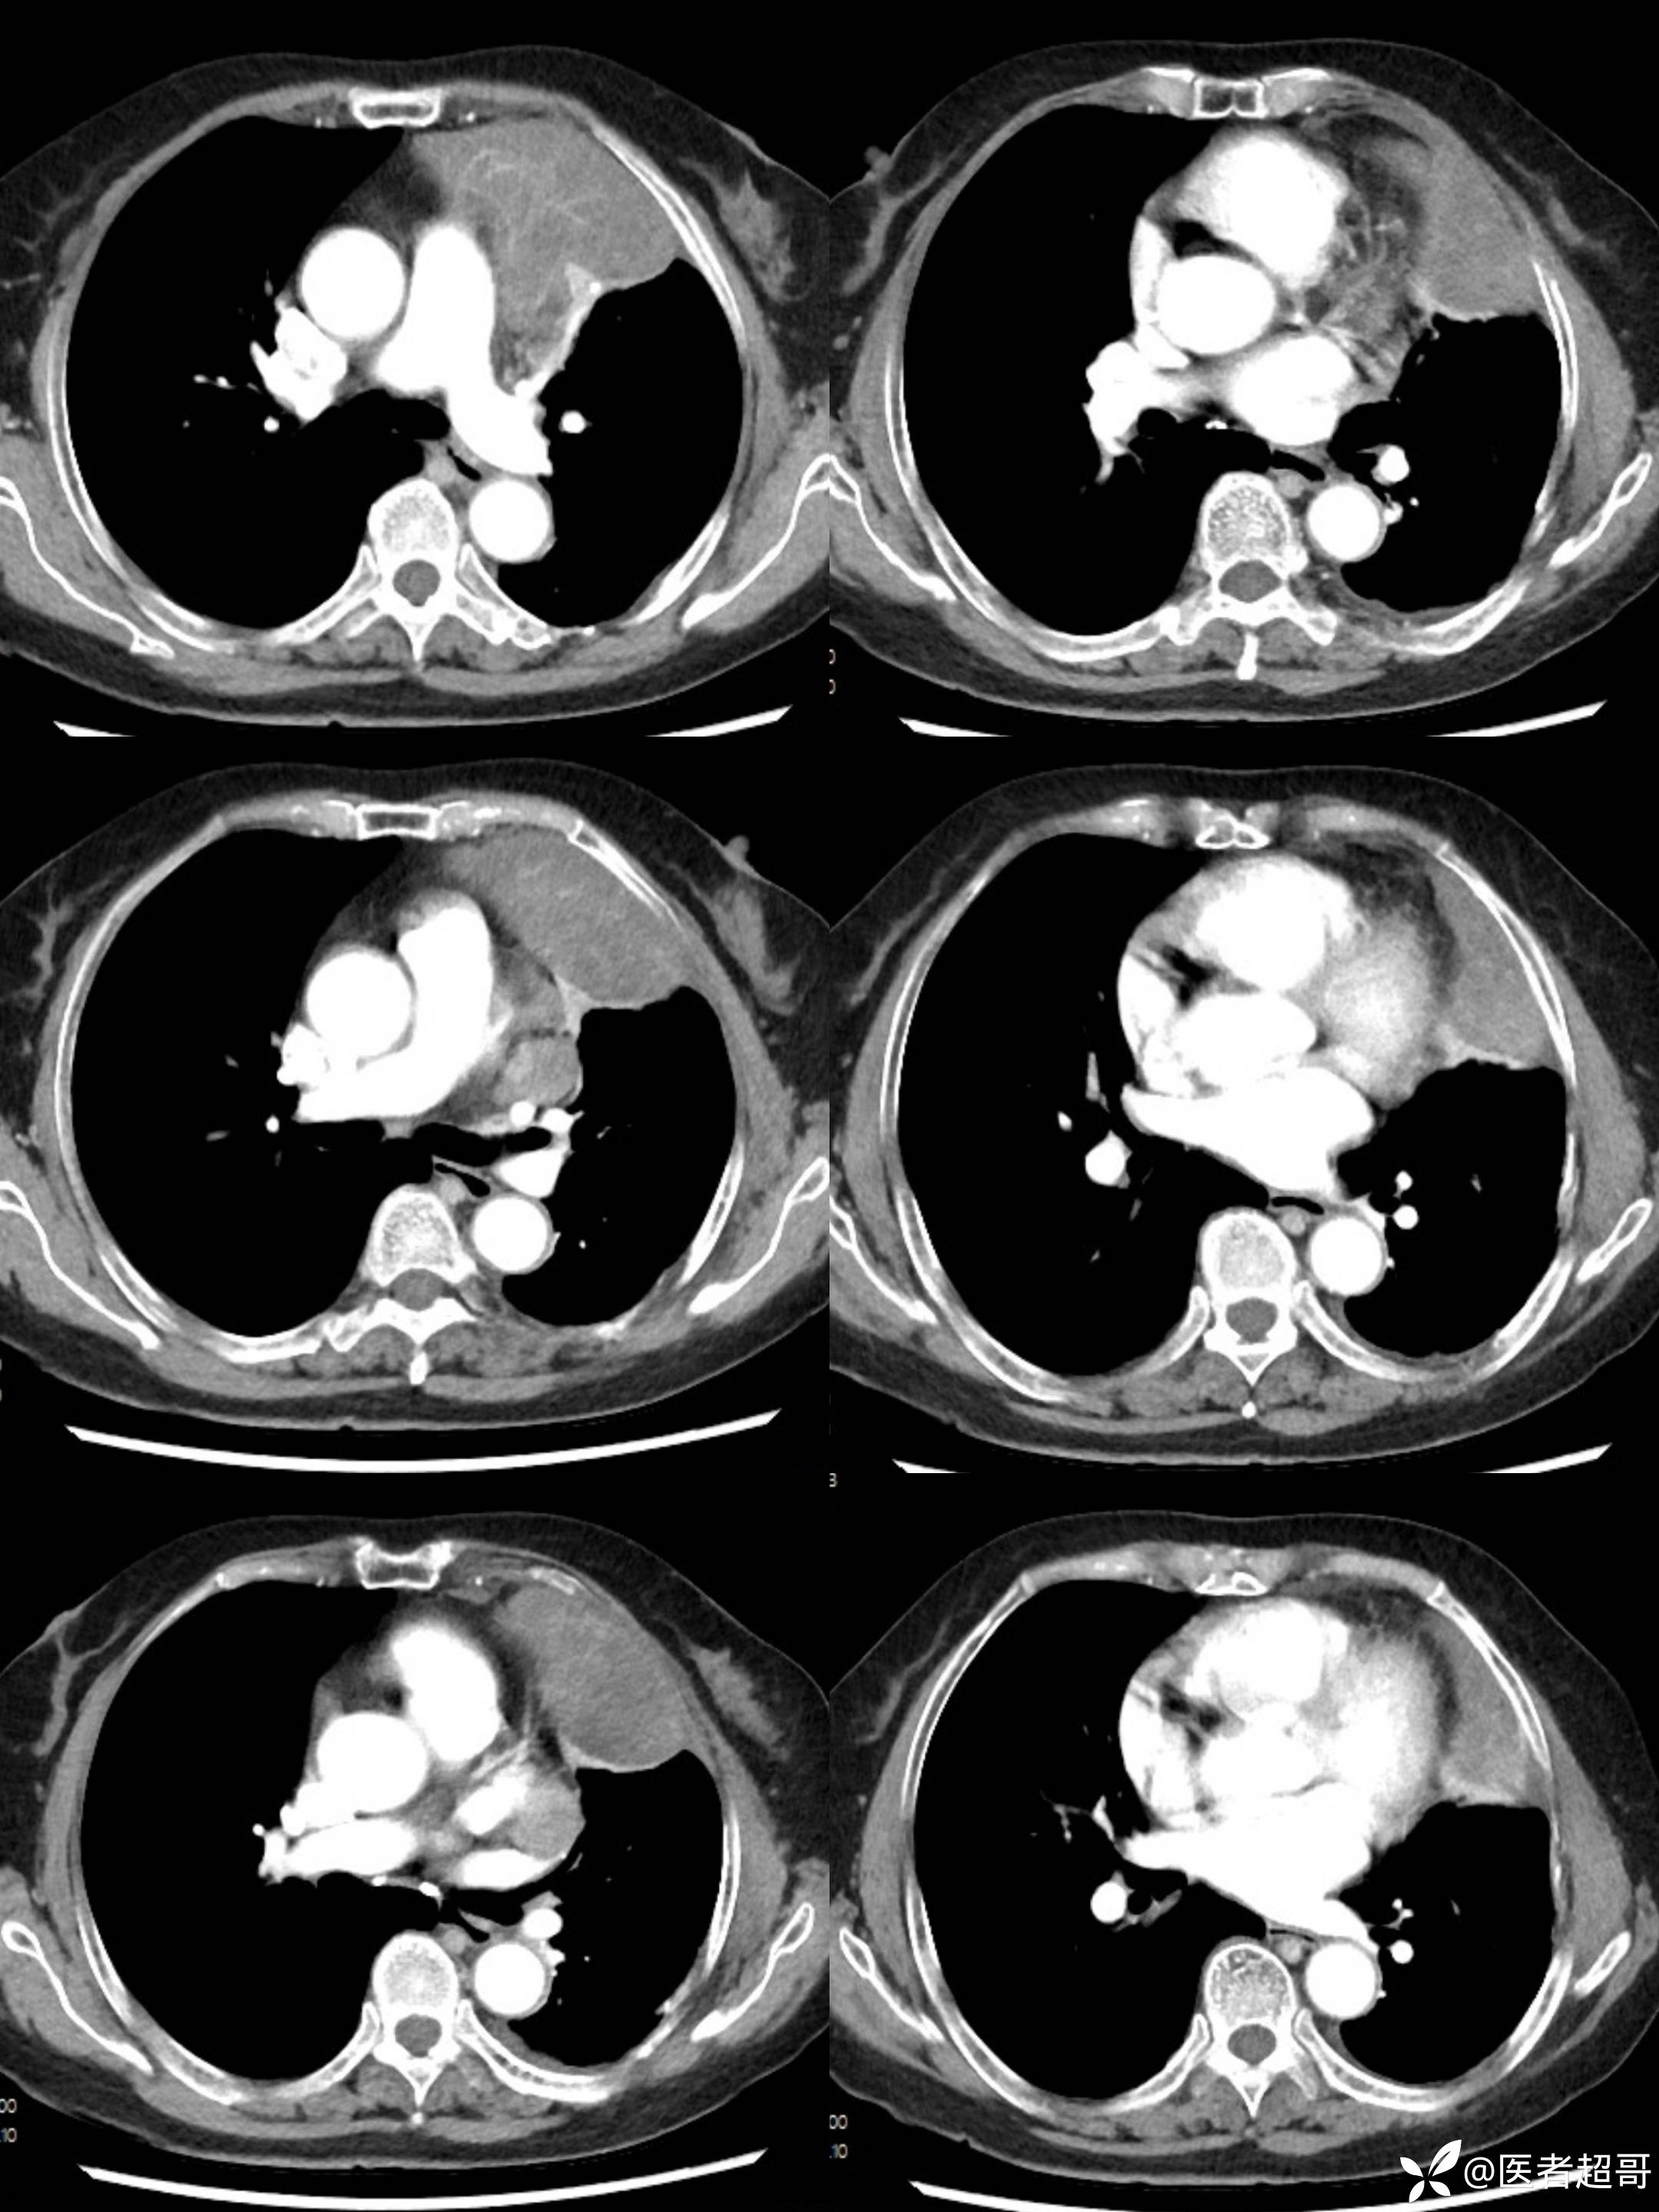

女73岁,体检发现左上纵隔占位1周

患者于1周前体检行CT检查提示:“左上纵隔见不规则团块状软组织密度影,大小约90*63mm”,患者平素偶有头晕,无明显胸闷气急,今为进一步治疗来我院就诊, 门诊以"左上纵隔肿物"收入院。

糖类抗原125(CA125):44.9(正常0-30.2),余实验室检查无殊